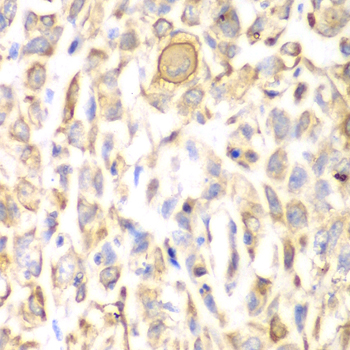

• A1930: image 3

Immunohistochemistry of paraffin-embedded human lung cancer using CD151 antibody at dilution of 1:200 (400x lens).